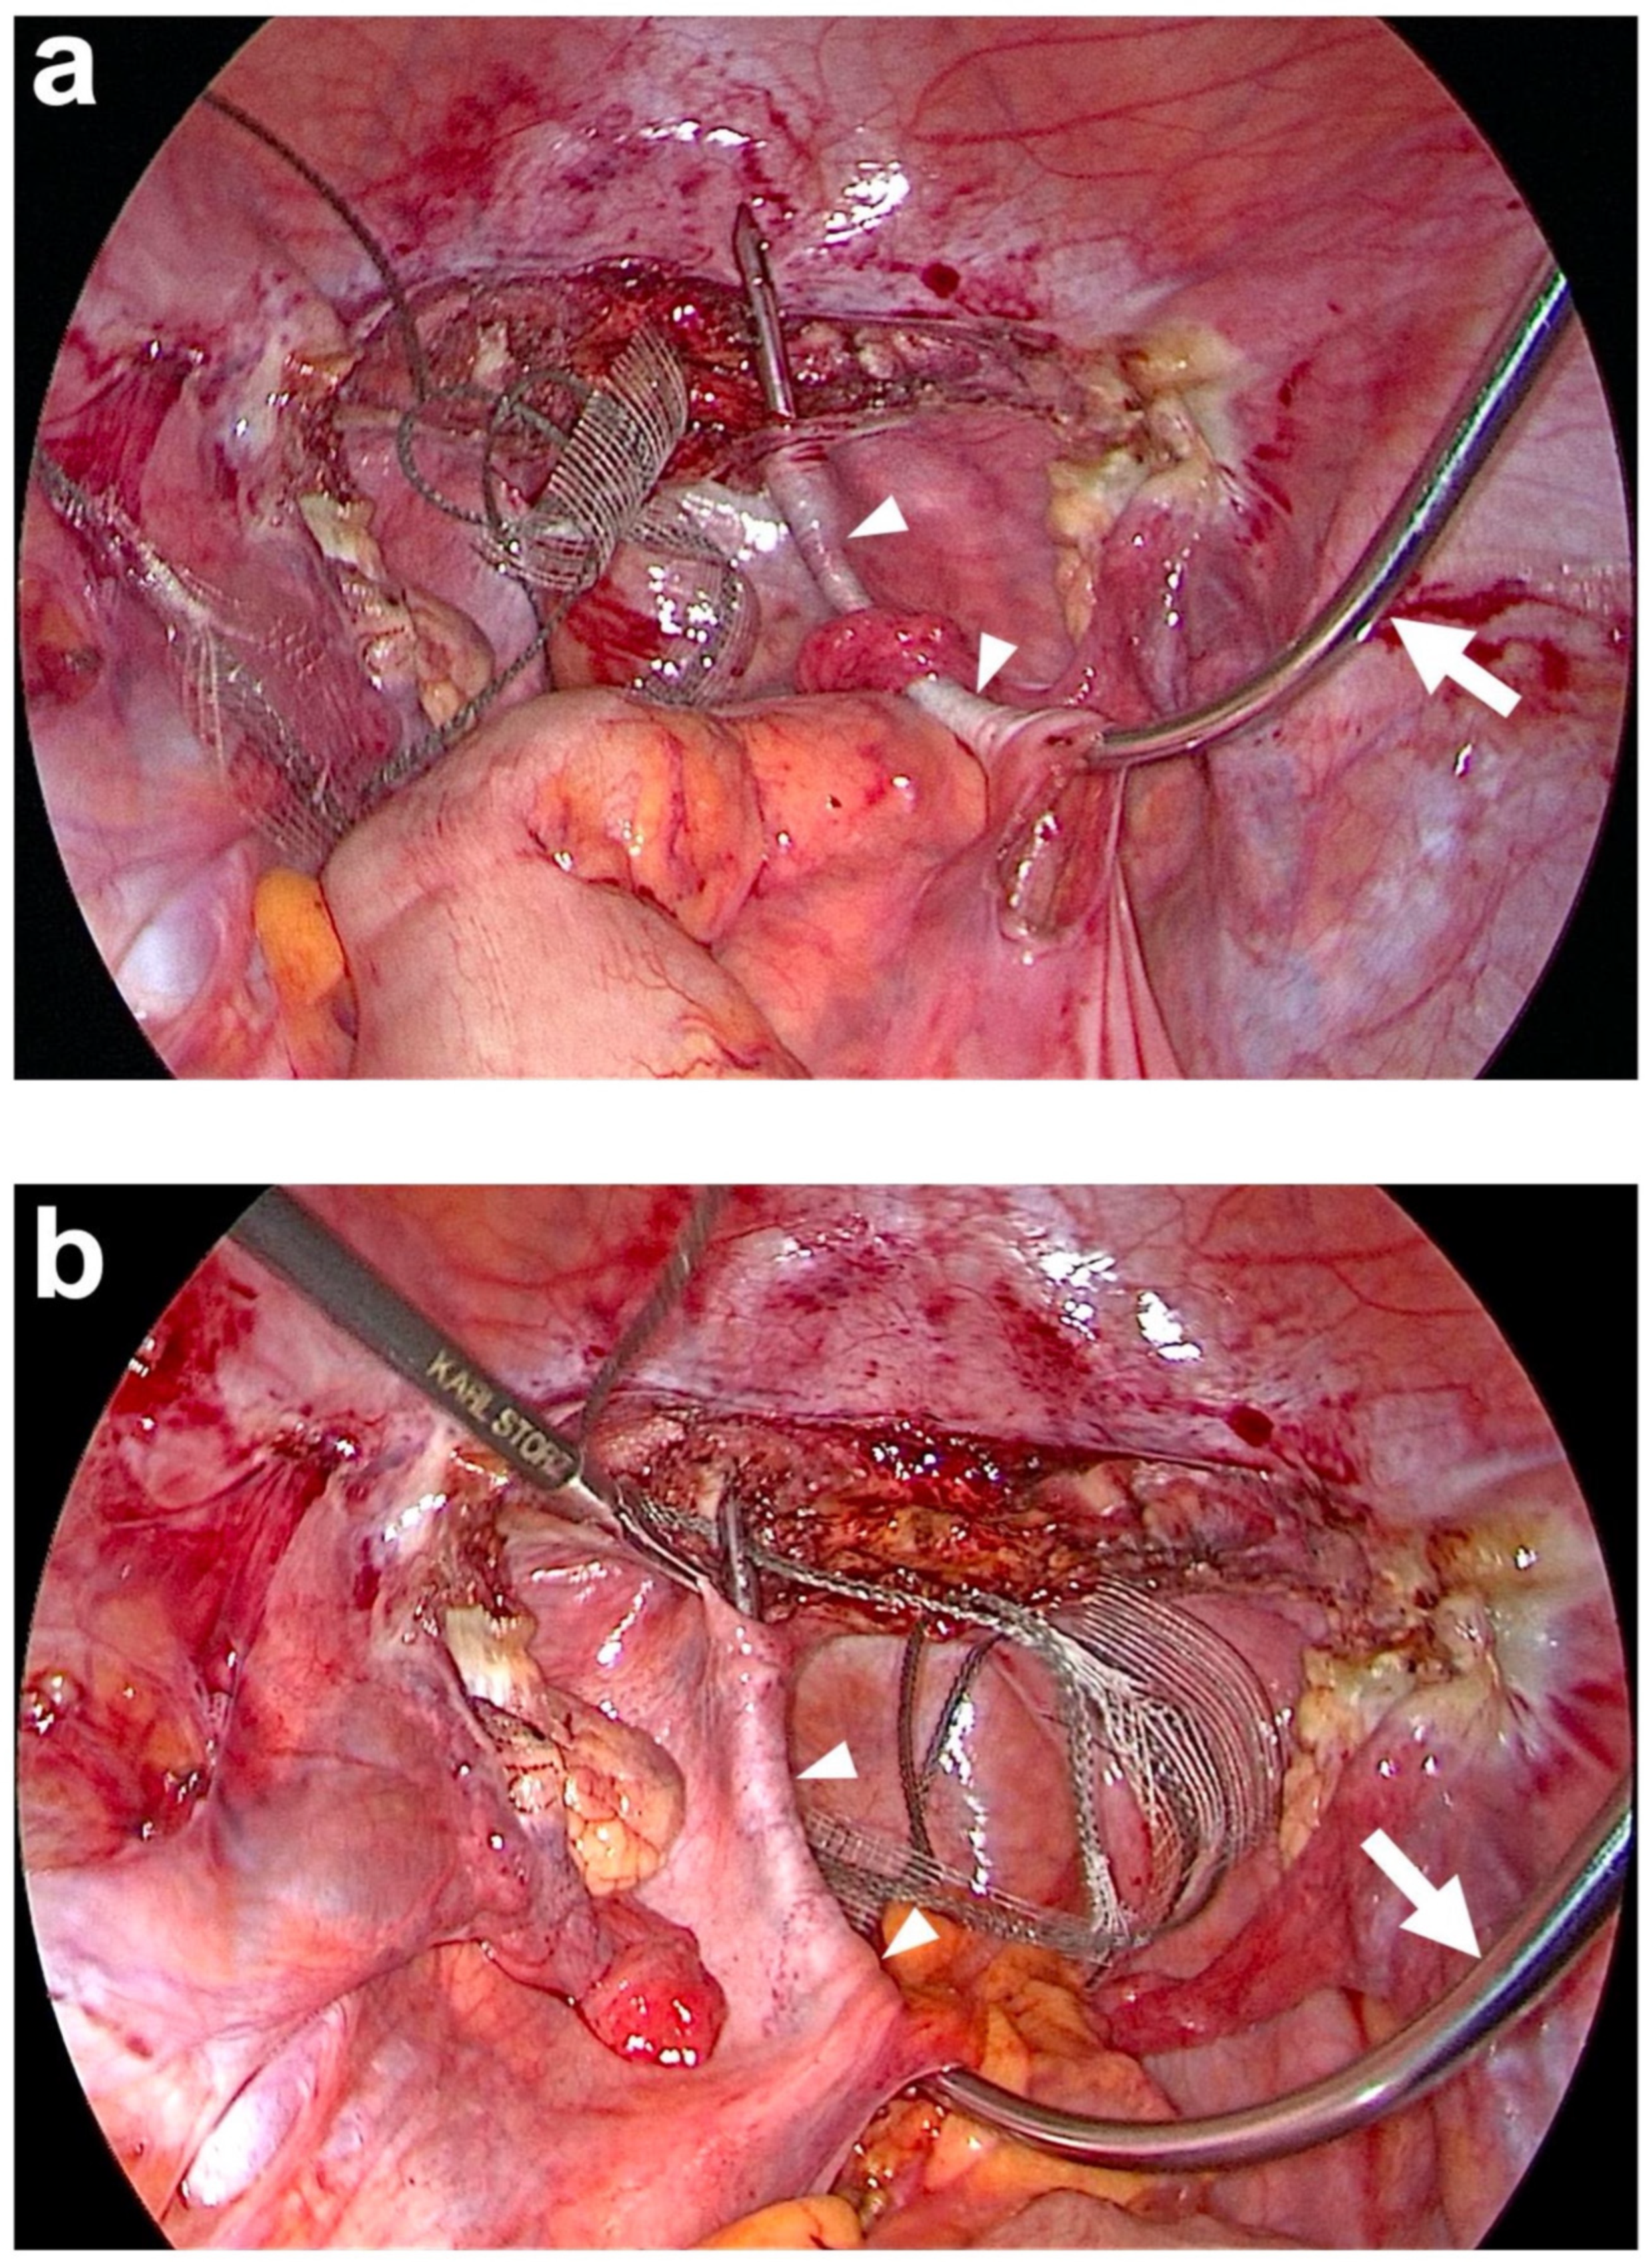

| Tunneling of both USL | The blunt tip of tunneling device is inserted into the left sacral peritoneal window and advanced under the peritoneum towards left paracervical tissue. Threading one lateral end of the PVDF structure through the hole of the tunneling device’s tip and pulling it back. Same procedure on the right side. | The blunt tip of tunneling device is inserted into the left sacral peritoneal window and advanced under the peritoneum towards the left paracervical tissue. Threading one lateral end of the PVDF structure through the hole of the tunneling device’s tip and pulling it back. Same procedure on the right side (Figure 6). |

| Posterior fixation of left and right arm of PVDF structure (Figure 1) | At left and right prevertebral fascial layer at S1 with 2 interrupted, non-absorbable sutures each e within the defined locations at the PVDF structure. | At left and right prevertebral fascial layer on S1/promontory with 3 titanium helices each g within the defined locations at the PVDF structure (Figure 2 and Figure 7). |